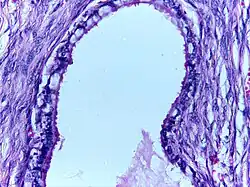

![]() | Serous cystadenoma | Histopathology of serous cystadenoma, with admixed scattered ciliated cells. This case closely resembles normal surface endometrial epithelium of the uterus | Category: Histopathology of ovarian serous cystadenoma | Ovarian cystadenoma |